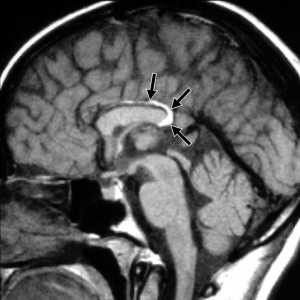

Ранее не описанный в литературе симптом «клубка в разрезе» («clew in cross-section»), выглядящий как несколько точек в гранулематозном очаге, представляющих свернувшуюся нематоду, наблюдался в 9 случаях из 11 поражения головного мозга круглыми червями (рис. 1-3); при этом во всех наблюдениях имелись уже известные специфические нейровизуализационные симптомы поражения мозга нематодами — симптомы «туннеля» и визуализация гельминта (помимо не во всех случаях наблюдаемого симптома «нитки бус»). Такая частота выявления нового симптома (81%) может уверенно говорить о его специфичности, без всяких статистических методов анализа.

Возникает вопрос, зачем нужен данный симптом, если имеются уже известные другие специфические радиологические симптомы. Валидность описываемого симптома «клубка в разрезе» наглядно демонстрирует следующее клиническое наблюдение.

Проведено МРТ головного мозга — заключение: «очаг ишемии в левой лобно-теменной области на фоне сосудистых аномалий». Очаг измененной интенсивности сигнала показан на рис. 4 (верхний ряд, правые снимки); «сосудистая аномалия» заключалась в умеренном сужении проксимального сегмента левой средней мозговой сонной артерии, сразу после отхождения от внутренней сонной артерии (не показано за неимением места в тексте статьи). На приведенных изображениях (рис. 4) отчетливо виден симптом «клубка в разрезе».

Так, у пациента на рис. 1 диагностирован «менинго- (поскольку был цитоз в ликворе) энцефалит неустановленной этиологии»; у пациента на рис. 2 — «острый рассеянный энцефаломиелит; мультифазное течение»; у пациента на рис. 3 — «менингеома» — видимо, дальнейшие комментарии не требуются…